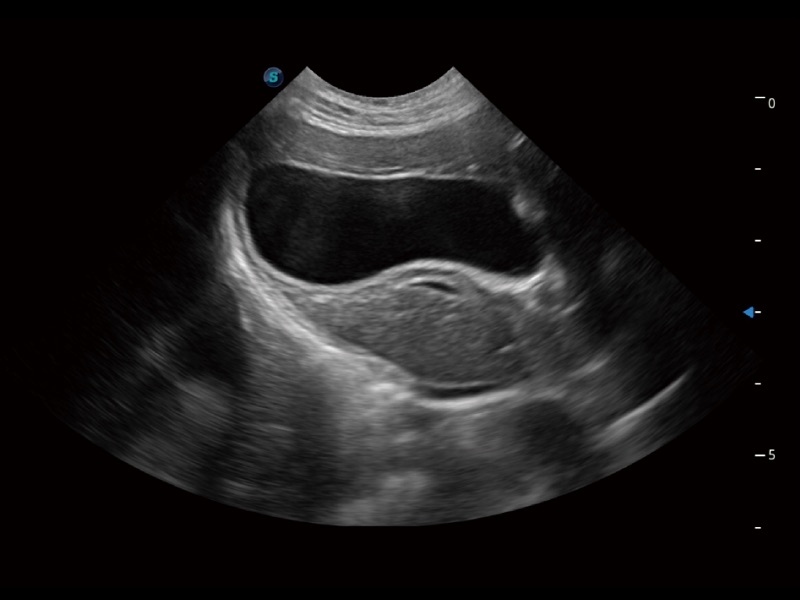

优异的基础图像

(猫)胆囊